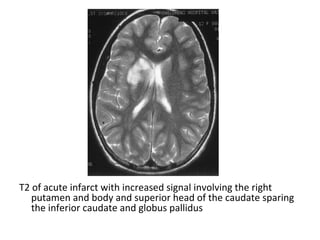

T2 of acute infarct with increased signal involving the right

putamen and body and superior head of the caudate sparing

the inferior caudate and globus pallidus